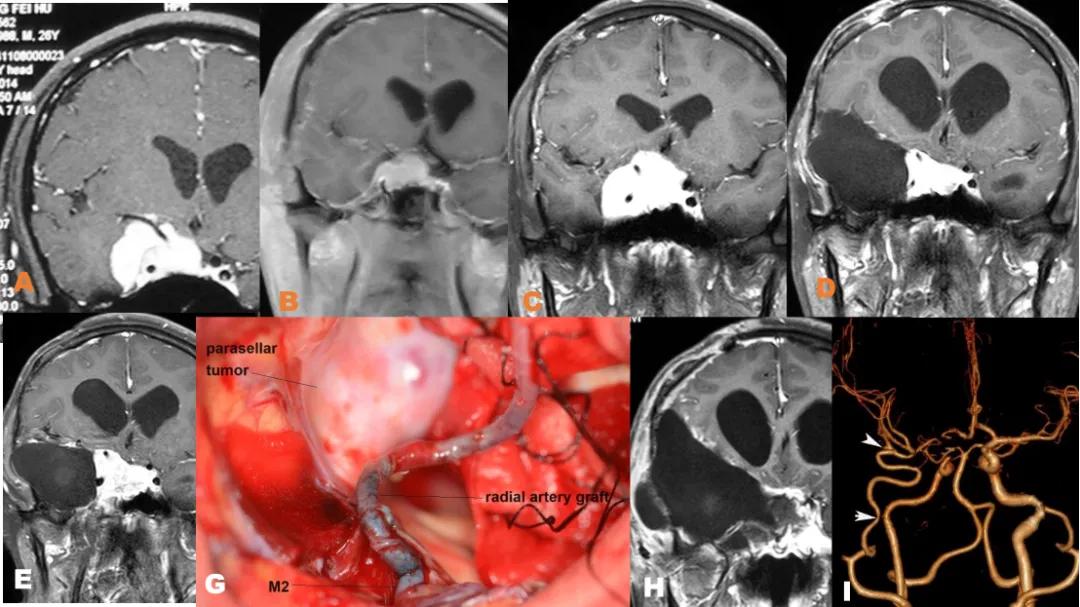

图9 26岁,男,右眼视物不清3个月,A磁共振冠状位显示右侧鞍旁肿瘤包裹颈内动脉;B第一次手术后,磁共振冠状位显示右侧鞍旁肿瘤颈内动脉外出切除,包绕颈动脉肿瘤残留;C术后4个月,再次出现头痛,视物不清,磁共振冠状位显示肿瘤再次生长,压迫视神经;D术后颞叶切除鞍内肿瘤,包绕颈内动脉,鞍内部分肿瘤未能切除。二次术后冠状磁共振显示包绕颈内动脉和鞍内肿瘤未能切除;E二次手术后8个月后,磁共振冠状位显示肿瘤再次生长,压迫视神经;G三次手术术中照片显示,桡动脉移植,颌内动脉搭桥后,鞍旁肿瘤;H三次手术后冠状磁共振显示肿瘤全切除;I术后CTA显示颌内动脉搭桥通畅,颈内动脉未显影。